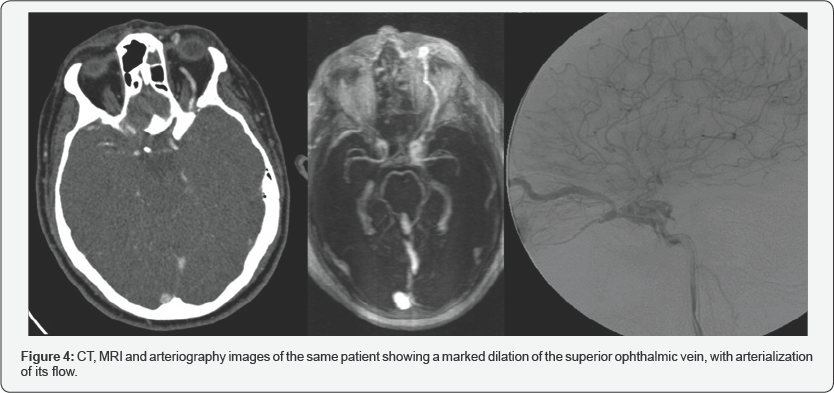

The drainage route can be multidirectional, both in the direct and in the indirect ones: anterior to the venous ophthalmic system (especially superior ophthalmic vein) as in (Figure4), posterior to the petrosal sinuses, lateral to the sphenoparietal sinus, contralateral to the cavernous sinus on the other side, or inferior to the pterygoid plexus. Thus, the manifestations may vary depending on the venous drainage route of the CCF.

CT is usually the initial test in the CCF study. The study by helical acquisition and 3D post-processing has contributed significantly to the diagnosis of this entity. The findings that we can observe in these studies and that allow us to establish the diagnosis of CCF are fundamentally an enlarged cavernous sinus that enhances asymmetric and early with an early filling of the plexuses, venous sinuses and ophthalmic veins (Figure 5). It also allows the evaluation of orbital signs such as proptosis and thickening of the extraocular musculature (Figure 6), and in cases of direct CCF, of traumatic etiology, it allows to identify the fracture traces in the skull base [5].

MRI angiography has been shown in several studies to be superior in the diagnosis and study of drainage. Like CT, MRI can also identify all signs of orbital involvement, such as proptosis and thickening of the extraocular musculature (Figure 7), as well as identifying cavernous sinus flow voids, which correspond to the angiographic finding of the contrast fill of the same when the contrast reaches the intracavernosal carotid. However, most authors agree that both CT and MRI cannot replace angiography at the moment of confirming the diagnosis, its classification, assessment of the type of drainage and its possible management [6-8].